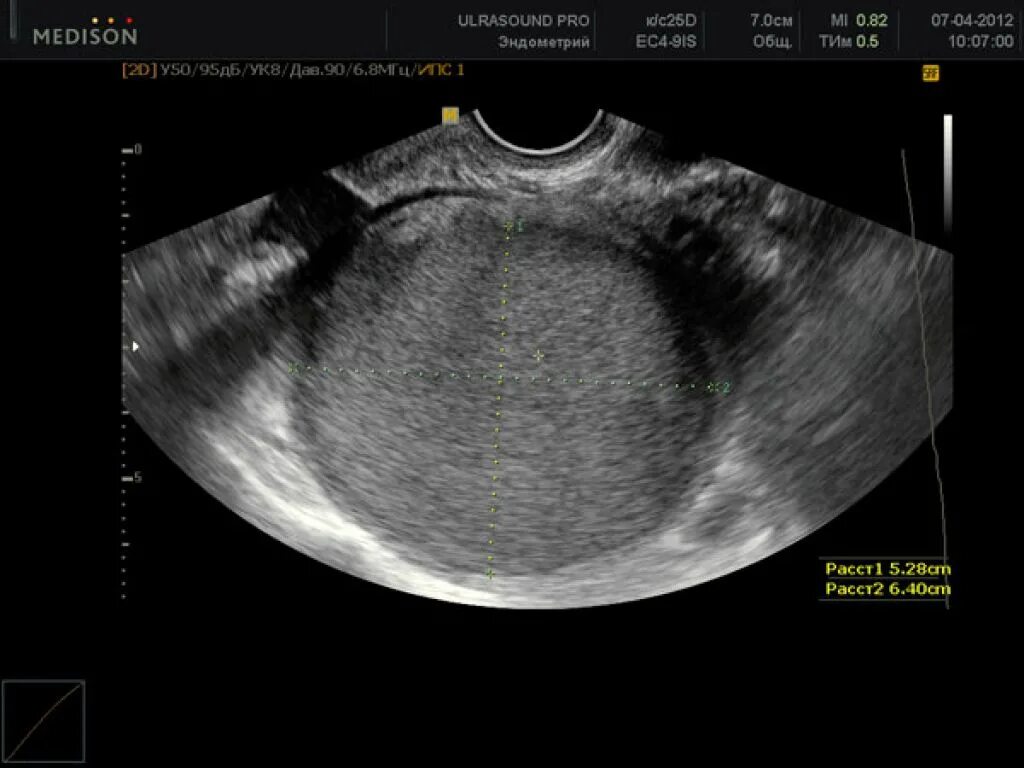

Как выглядит яичник